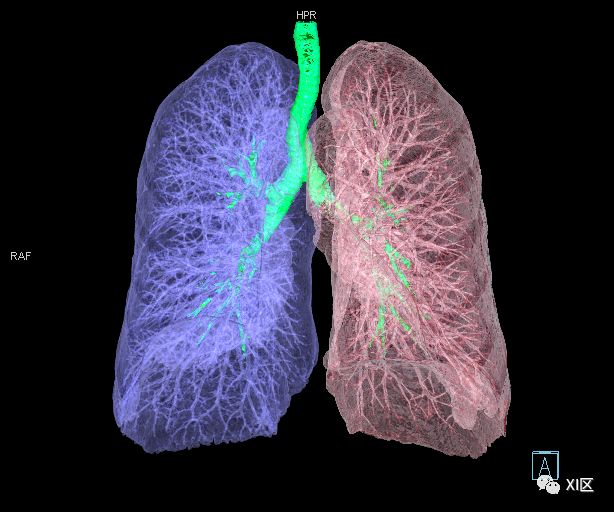

气管支气管树与两肺融合显示

气管树与左右肺的关系